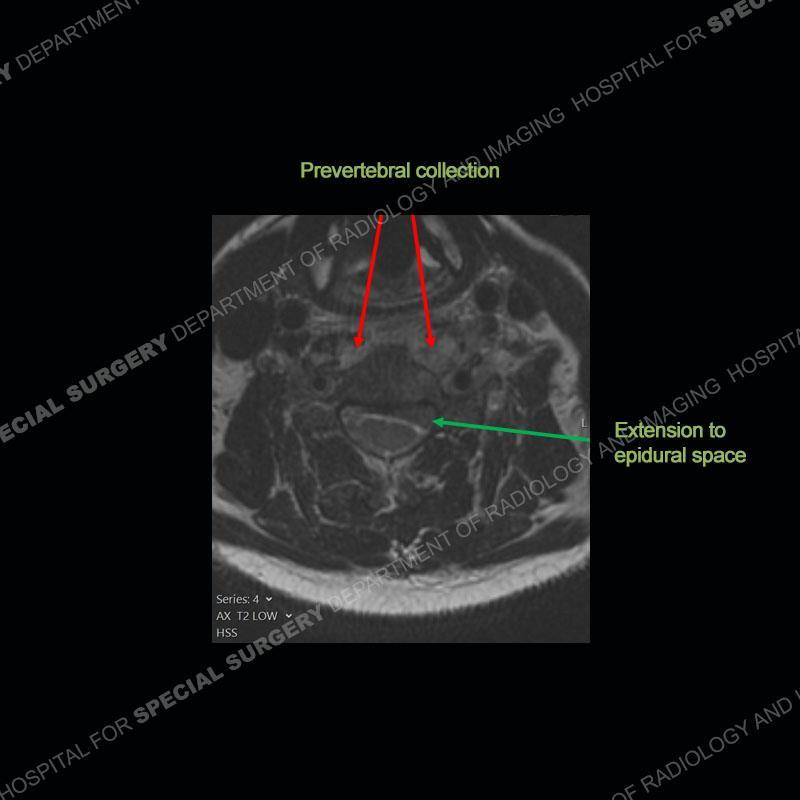

The radiographs demonstrate a prevertebral soft tissue fullness centered at C5-C6 that persists even on extension. There is a slight loss of disc height at C5-C6. The CT more readily shows the prevertebral soft tissue swelling at C5C6 where there is a punctate focus of gas. On the MRI, there is a marked amount of edema and a heterogeneous collection in the prevertebral soft tissue at C5-C6. Edema is present of the C5 and C6 vertebral bodies with a loss of the normal architecture about the disc space. A heterogeneous epidural collection has formed that causes compression of the spinal cord asymmetric to the left side and also precipitates severe left sided neural foraminal stenosis.